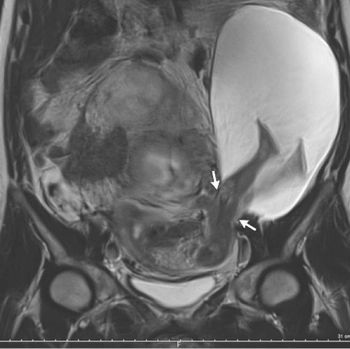

Kasus langka ini dipublikasikan dalam sebuah laporan di The New England Journal of Medicine. Seorang perempuan 33 tahun hamil dan memiliki robekan 2,5 cm di dinding rahim, hingga sebagian dari ketuban dan bahkan kaki janin keluar dari tempatnya.

Sang ibu tidak mengalami gejala apapun sebelumnya. Kondisi yang mengejutkan para dokter ini baru terungkap saat dilakukan pemeriksaan ulrasonografi pada pekan ke-22 kehamilan.

Dipastikan, robekan di rahim pasien bukan terjadi akibat tendangan sang bayi. Menurut hasil penelusuran, pemicunya adalah riwayat pasien yang pernah melahirkan sesar sebanyak 5 kali sebelumnya. Dinding rahimnya melemah dan robekan terjadi di dekat lokasi sayatan pada operasi sesar yang terakhir.

Meski berisiko, sang ibu dan pasangannya memutuskan untuk tetap melanjutkan kehamilannya. Dikutip dari Livescience, Jumat (23/12/2016), robekan membesar hingga 5 cm pada pekan ke-30, dan bukan lagi hanya kaki si bayi yang keluar bersama ketuban melainkan juga perutnya.